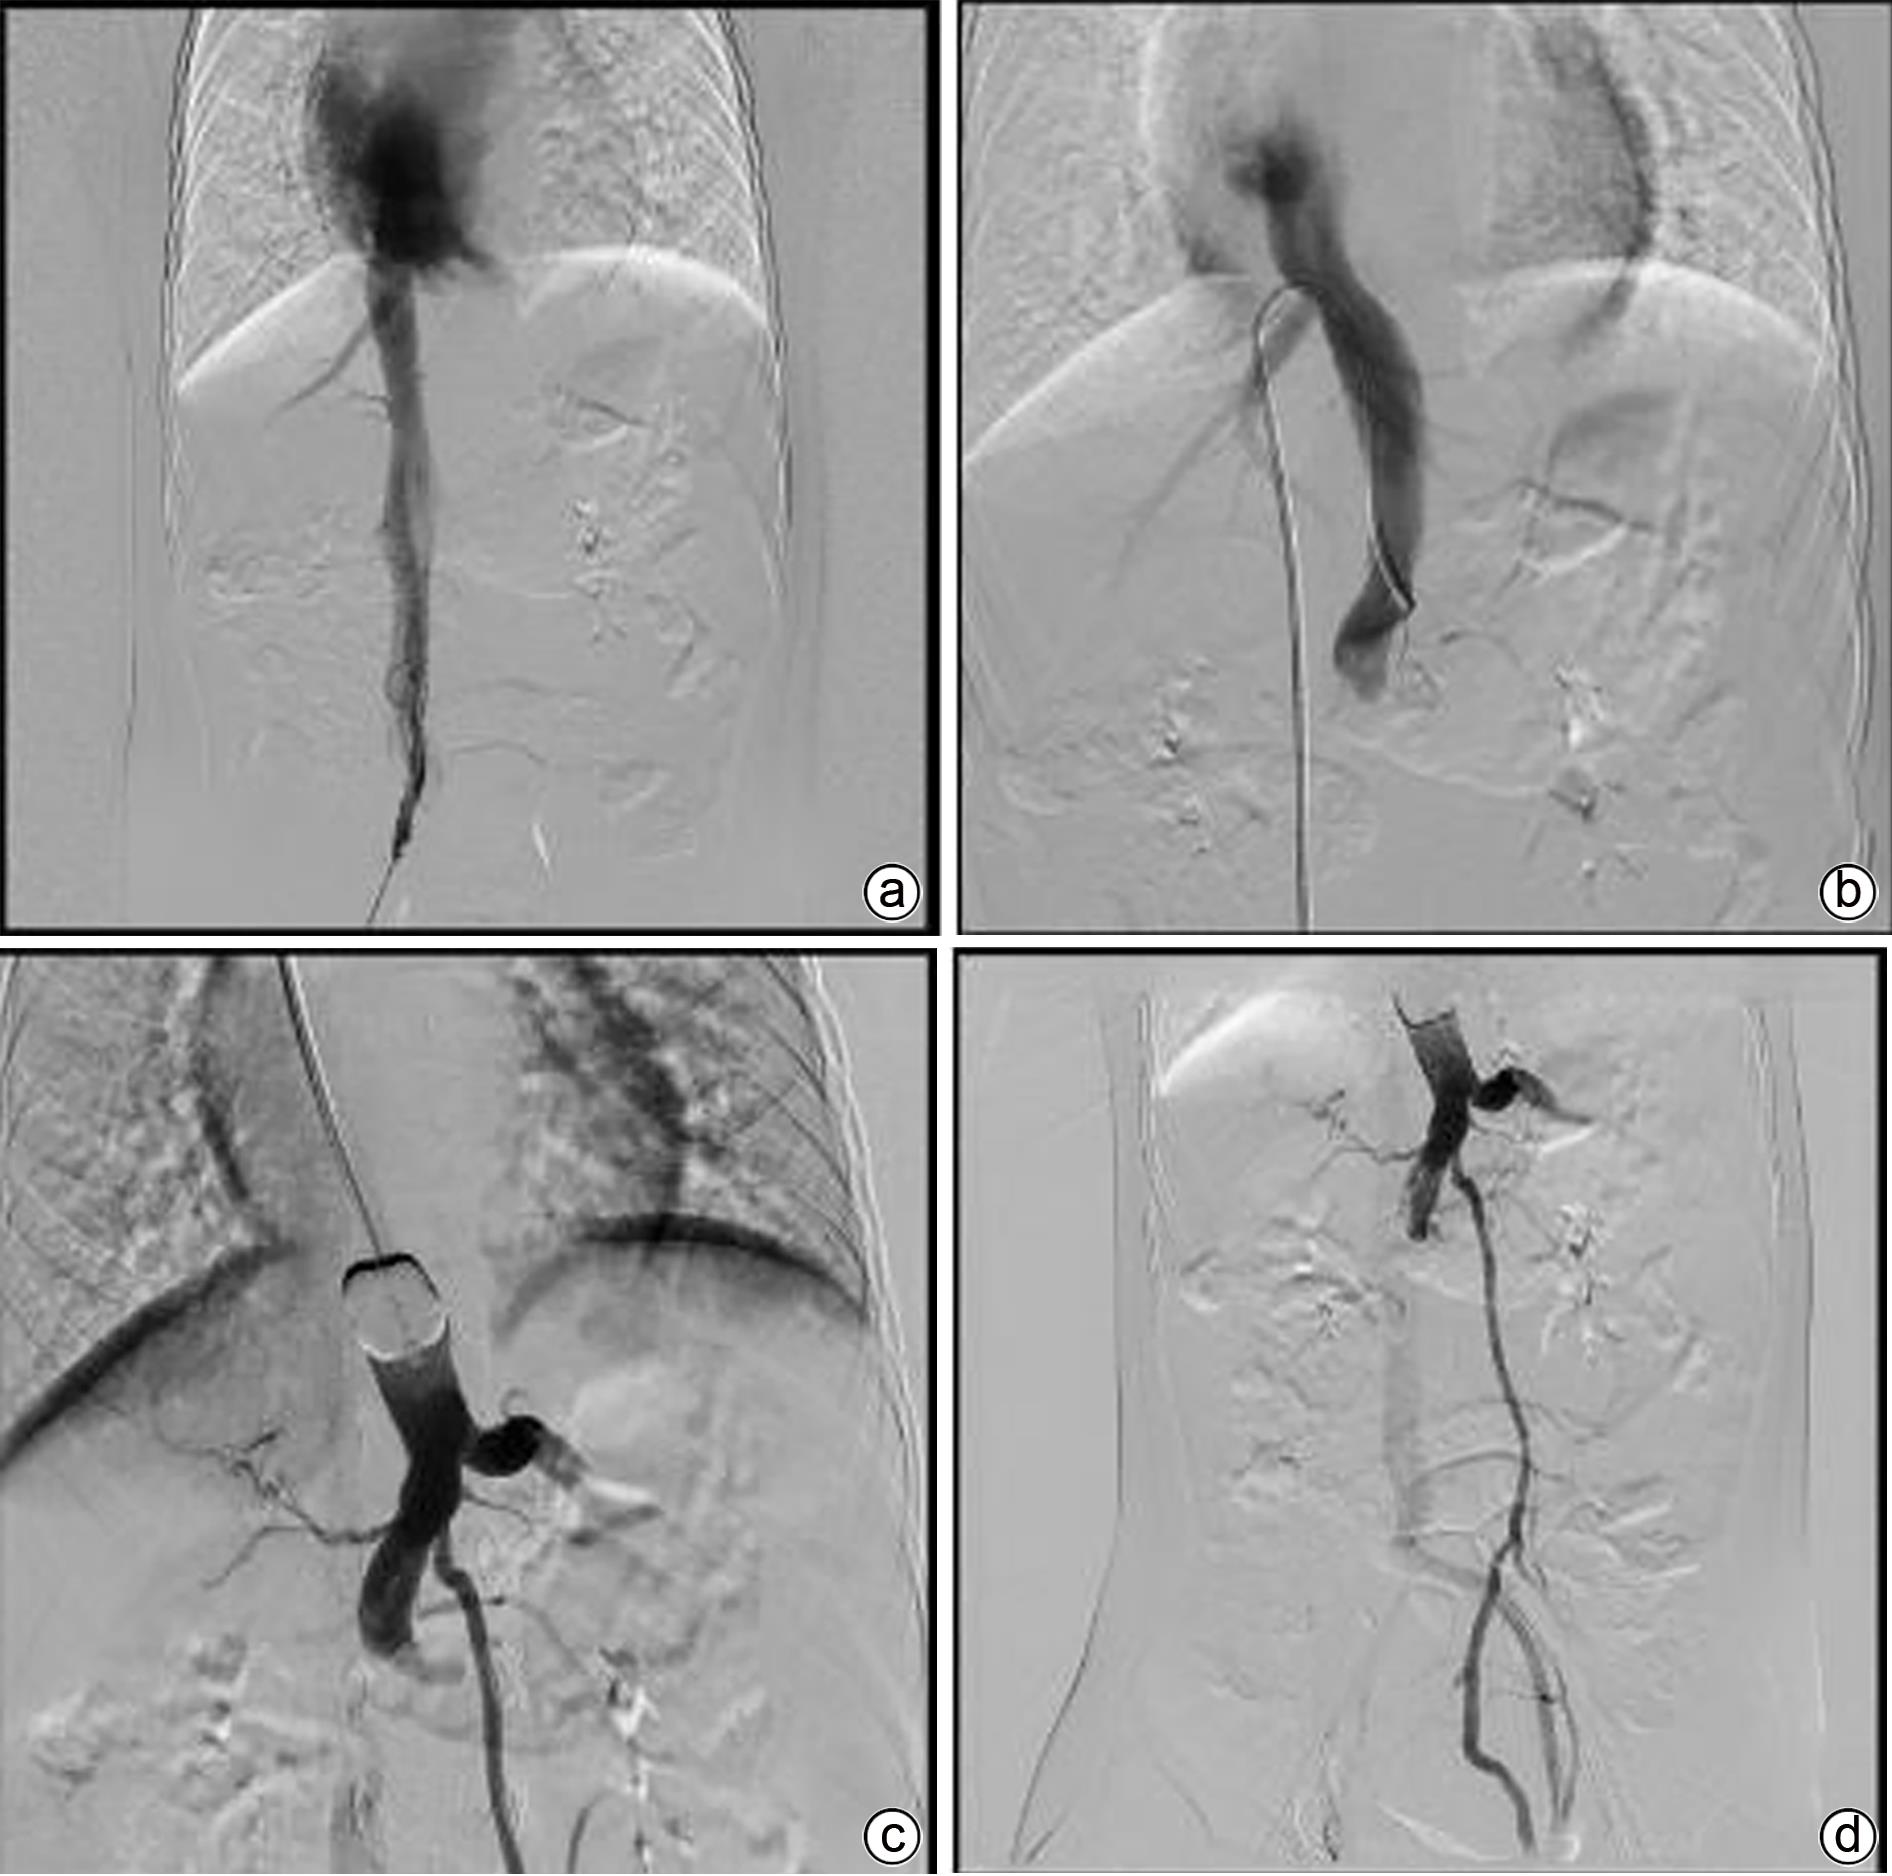

Transcatheter closure of rare type Ⅱ Abernethy malformation with pulmonary hypertension in children: A case report

Heng ZHANG, Bin JIANG, Zhicheng FANG, Zhongji MENG, Enfu DU

2023, 39(11): 2663-2667. DOI: 10.3969/j.issn.1001-5256.2023.11.022

Abstract(978) HTML (281) PDF (1074KB)(76)

Abstract:

Abernethy malformation, also known as congenital portosystemic shunts, is rare in clinical practice, with less than 300 cases reported in the global literature up to 2019. The disease can have serious complications such as pulmonary hypertension, liver tumor, and liver failure and tends to have an extremely poor prognosis, and early diagnosis and active and effective treatment can reduce and delay the onset of complications. In this case, portography combined with balloon occlusion helped to display the underdeveloped slender portal vein with dysplasia, so that the child who was formerly misdiagnosed with type Ⅰ Abernethy malformation was diagnosed with type Ⅱ Abernethy malformation, and then the child was successfully treated by transcatheter closure. This article gives a detailed report of this case.